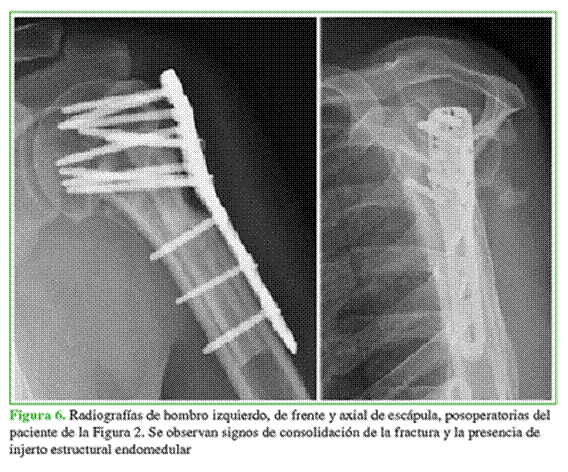

Se utilizó aloinjerto estructural de radio en 10 casos y de cúbito en dos casos, provenientes del banco de huesos de nuestro Centro. Luego de visualizar una reducción correcta y estable en el intensificador de imágenes, se aplicó una placa bloqueada anatómica para húmero proximal AZ (South America Implants, Buenos Aires, Argentina). Se fijó la placa con tornillos corticales bloqueados que atravesaban el AOEE y, siempre que fue posible, al menos, un tornillo con dirección al calcar (Figuras 5 y 6).

La evaluación radiográfica estuvo a cargo del mismo evaluador (N. N. A.), con las imágenes preoperatorias, junto con las del primero y último control posoperatorio, en la proyección anteroposterior de Grashey. En las radiografías preoperatorias, se evaluó el tipo de fractura según la clasificación de Resch, se obtuvo la medida del GCHP (Figura 7), cuyos resultados <6 mm se asocian con osteoporosis.